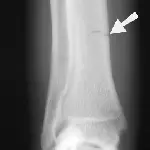

Figure 4A. A 5-year-old, male Brittany spaniel with a 2-month history of lameness. The opposite elbow was normal. A fracture line cannot be seen in this anteroposterior view of the elbow.

Figure 4B. A hairline intercondylar fracture (arrow) can be seen after repositioning the elbow and x-ray beam only slightly. This may represent incomplete ossification or a true fracture. In this case, the hairline fracture was confirmed by bone scan and arthroscopy.